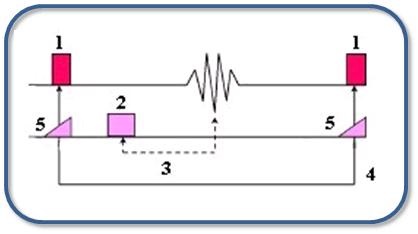

SPGR is a GRE sequence that uses continuous phase shifting of the RF excitation pulse to spoil residual transverse magnetization. The RF spoiler pulse, minimum TE, short TR (40 to 60 ms), and moderate flip angle (30 to 50°) result in T1-weighted image contrast. SPGR is available in 2D sequential and 3D modes.

| Number | Description |

|---|---|

| 1 | Variable pulse |

| 2 | Gradient pulse |

| 3 | TE |

| 4 | TR |

| 5 | Phase shift |